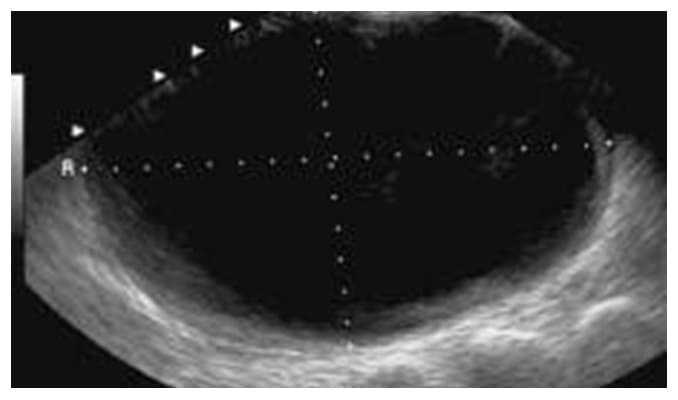

Los quistes de ovario son tumoraciones de contenido líquido, contenido dentro de los ovarios, pueden ser de "agua", "moco" o "sangre" dependiendo del tipo de quiste que se presente y en algunos casos puede ser mixto (contenido líquido y sólido) como los teratomas.

Quistes de Ovario